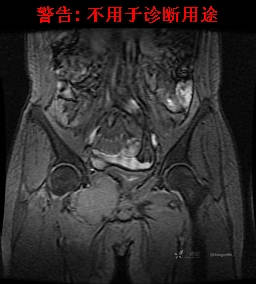

现病史:患者2022-02-07在市中医院体检发现右肺占位,胸部CT示:右肺下叶基底段见一不规则软组织密度影,增强扫描呈轻中度强化,可见血管贴边征。当时无任何不适。2022-02-24于省肿瘤医院行纤支镜检查阴性,痰检未找到癌细胞。经皮肺穿刺细胞学检查找到高度癌疑细胞,病理示:右下肺穿刺考虑神经内分泌癌。免疫组化结果:CgA(-)、CD56(-)、Syn(+)、CK广谱(-)、p40(-)、P63(少量+)、TTF-1(-)、Ki-67(+,40%)、NapsinA(-)、Calcitonin(-)、TG(-)。ECT示:全身骨扫描未见明确骨转移征象。患者出现贫血且逐渐加重、低蛋白血症,予人促红素注射液、精蛋白重组人胰岛素混合注射液、人血白蛋白对症处理,效果不明显,病情加重,右髋出现疼痛,不能行走。2022-03-04转院南大二附院进一步治疗,2022-03-20行右侧髂骨穿刺活检术,术后病理结果示:考虑软组织透明细胞肉瘤。免疫组化示:瘤细胞Vim(+)、NSE(+)、S-100(+)、SOX10弱(+)、Melan-A(+)、TFE-3部分弱(+)、CK(-)、MyoD1(-)、Desmin(-)、HMB45(-)、CD34(-)、CD68(-)、CR(-)、Ki-67约15%(+)。特殊染色示:网状纤维染色(-)、PAS(±)。

2022-03-05血常规示:血红蛋白:64g/L,生化示:白蛋白20g/L。骨髓涂片细胞学检查示:骨髓增生明显活跃,粒红比减低。粒、红、巨三系增生明显活跃。粒系伴成熟障碍。髓片浆细胞较易见,占7%。粒系增生明显活跃,核明显左移,可见巨幼样变及核浆发育不平衡。PET-CT示:1.右肺下叶软组织肿块、右侧耻骨下支及耻骨联合处骨质破坏伴软组织肿块形成,FDG代谢均异常增改,考虑恶性病变,建议病理检查;右侧髂血管旁、双侧腹股沟淋巴结反应性增生,建议随访。2.多浆膜腔(双侧胸腔、心包腔、盆腔)少量积液。3.全身骨骼FDG代谢弥漫增高,考虑骨髓反应性增生。4.大小肠条片状FDG代谢增高,考虑生理性摄取。5.右侧上颌窦面膜下囊肿,脑部FDG代谢未见明显异常。6.C7-T1层面后纵韧带钙化。患者乏力加重,卧床不起,不能承重,大小便不顺畅,转院至我院。门诊拟“1.右肺占位并右侧骨盆转移2.低蛋白血症3.中度贫血 4,血糖升高(原因待查)”收入住院。患者发病以来,无胸闷、胸痛,无呼吸困难,偶咳嗽,无咳血,饮食、睡眠欠佳,2个月之内体重减轻约10kg。

右骨盆及双下肢未见畸形,皮温正常,无浅静脉怒张,右腹股沟中点可触及一质韧肿物,大小约6cm*4cm*5cm,边界不清,固定、压痛明显,叩击痛阳性。右髋关节外旋、屈曲受限。右髋4字试验阳性,左侧阴性,双下肢直腿抬高试验阴性。感觉、运动正常,末梢血运良好,生理反射存在,病理反射未引出。